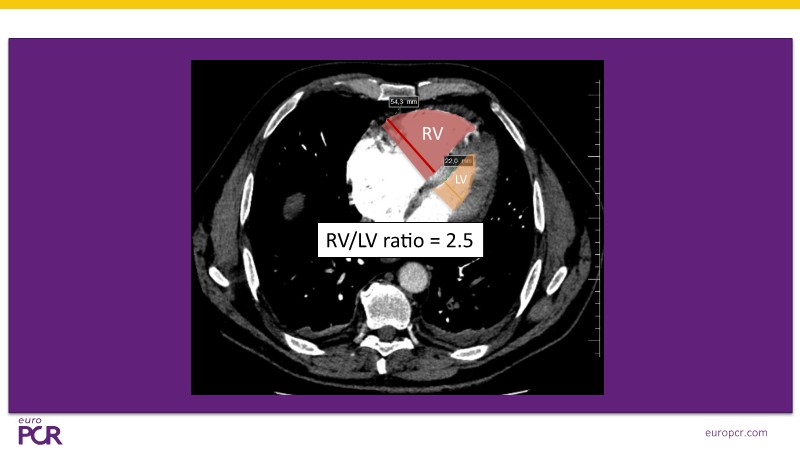

Discover a streamlined approach to pulmonary embolism treatment in this EuroPCR 2025 session. Learn how ultrasound-assisted thrombolysis improves right ventricular function and pulmonary perfusion while enabling timely reperfusion with low-dose thrombolytic therapy delivered directly to the clot. Explore the latest data from the HI-PEITHO randomised trial and review real-world cases that highlight patient selection and the practical application of catheter-based reperfusion strategies. With its minimally invasive profile, low complication rates, and straightforward logistics, the EKOS system offers a clinically sound and efficient solution to PE management.